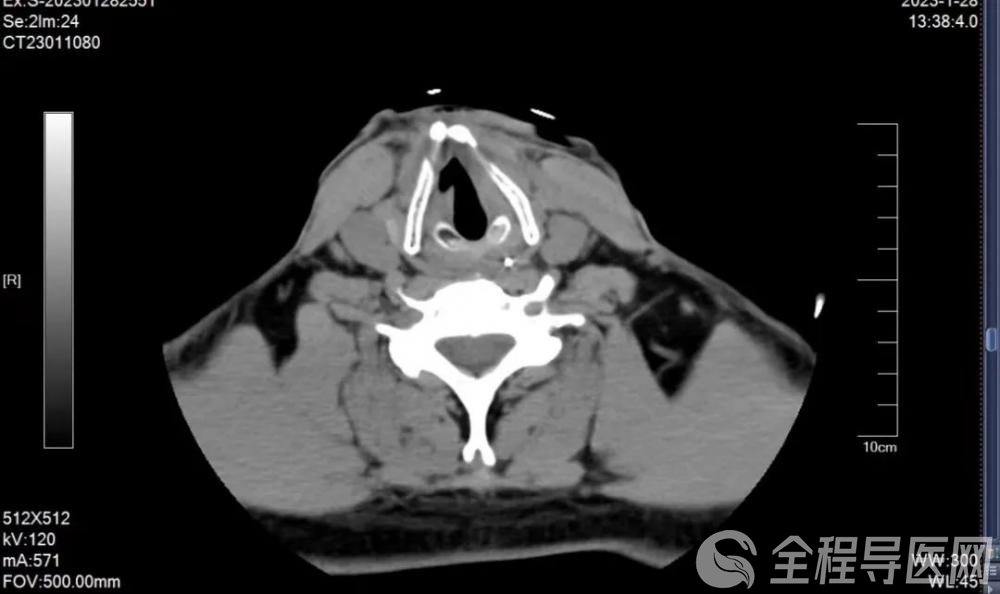

患者术后影像资料

气管切开顺利完成!

喉功能重建顺利完成!

颈部清创缝合顺利完成!

1周后,患者接受了气管瘘闭合手术。“手术非常成功!术后伤口愈合良好!患者的呼吸、吞咽、发音、屏气等各项喉功能完全恢复正常!”王浩高兴地表示,“作为医者,经过治疗患者能够完全康复,就是对我们的最大慰藉!”